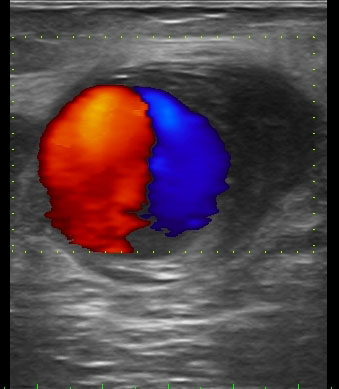

SIGNO DEL YIN YANG

Es un signo visible en ecografía con doppler color, que representa el flujo bidireccional o en remolino que ocurre en un pseudoaneurisma. La imagen corresponde a una paciente con antecedente de punción de la arteria femoral para realización de un cateterismo. Cinco días más tarde acude a urgencias por abultamiento doloroso en la región inguinal. A la palpación se percibía un thrill.

El pseudoaneurisma es una lesión de la pared vascular en la que se produce una fuga de sangre a un espacio contenido por la adventicia del vaso y/o una fascia circundante. La sangre entra y sale de dicho espacio por un mismo orificio, el cuello, lo que justifica el flujo en remolino. En doppler, el color azul o rojo indica la dirección del flujo, que se acerca o aleja del transductor.

El nombre del signo hace referencia al conocido símbolo ancestral del taoísmo que representa la naturaleza dual de todos los elementos del universo, que están compuestos por fuerzas opuestas pero complementarias.

A este signo también se le ha llamado Signo de Pepsi, por el parecido de la imagen con el logotipo de la conocida bebida de cola. Sin embargo, este nombre no ha cuajado en la práctica radiológica.